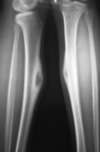

Giant Cell Tumor (GCT) Key Criteria - Physis MUST be closed - Non Sclerotic Border - Abuts the articular surface

26

Giant Cell Tumor (GCT)

20-30 = physis closed (MUST) Location: Knee - Most common Association: ABC (can turn into them) Quasi malignant (5% - lung mets) Fluid levels on MRI